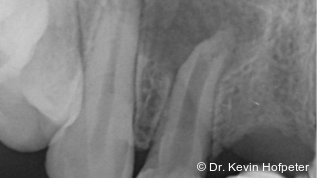

Zu den wesentlichen diagnostischen Verfahren, die zur Erfassung des Pulpastatus herangezogen werden, gehören neben der Inspektion und der röntgenologischen Bildgebung die Sensibilitätsprüfung sowie der Perkussionstest. Der Inspektion kommt insbesondere bei der Erstbehandlung eine wesentliche Rolle zu. Hierbei wird abgeklärt, ob es sich bei Zahnfrakturen um eine schmelzbegrenzte Verletzung handelt, ob das Dentin mitbetroffen und ob zusätzlich die Pulpa exponiert ist. Bei Dislokationsverletzungen wird das Ausmaß der Positionsveränderung erfasst und ob zusätzliche Gewebe wie Knochenstrukturen oder umliegende Weichgewebe betroffen sind. Auch können Farbveränderungen des Zahnes erfasst werden. Die Röntgendiagnostik zum Zeitpunkt des Unfalles gibt Aufschluss über die Größe des Pulpenkavums und das Lumen des Wurzelkanals, den Stand des Wurzelwachstums und die periapikalen Verhältnisse. Des Weiteren finden sich möglicherweise Hinweise auf eine Wurzelfraktur.

Zu den Zahnfrakturen mit Pulpabeteiligung gehören die in das Dentin reichende unkomplizierte Kronenfraktur sowie die komplizierte Kronenfraktur mit Pulpaexposition. Rein schmelzbegrenzte Frakturen sind hinsichtlich des Pulpastatus als unkritisch einzuschätzen.1 Dislokationsverletzungen betreffen die Pulpa insofern, als das Gefäß-Nerv-Bündel je nach Ausprägung der Positionsveränderung gestaucht, gedehnt oder abgerissen sein kann. Bei Zähnen mit abgeschlossenem Wurzelwachstum geht man davon aus, dass spätestens ab einer Dislokation von 2 mm die Pulpa abgerissen wurde, was die zeitnahe Einleitung der Wurzelkanalbehandlung notwendig macht.2, 3 Bei geringer ausgeprägter Dislokation kommt den Nachkontrollen eine wesentliche Rolle zu, bei denen jeweils dem Pulpastatus besonderes Augenmerk zukommen sollte, um eine Pulpanekrose frühzeitig zu detektieren.

Bei ausgeprägten Dislokationsverletzungen stellt die Schädigung des Parodonts die dominierende Verletzung dar, die auch zu Spätfolgen und Komplikationen führen kann. Verletzungen des Endodonts sind im Hinblick auf den Zahnerhalt vergleichsweise unbedeutender, da die Wurzelkanalbehandlung eine Infektion relativ sicher verhindern oder beseitigen kann. Die Erstversorgung schließt im Wesentlichen die Repositionierung und Schienung zur Ruhigstellung der betroffenen Zähne ein.3 Spätestens ab einer Positionsveränderung von 2 mm ist bei Zähnen mit abgeschlossenem Wurzelwachstum sicher von einem irreparablen Schaden der Pulpa auszugehen.2 Wichtig ist es, zeitnah, in der Regel während der Schienungsdauer, die Wurzelkanalbehandlung einzuleiten, um eine bakterielle Besiedelung des Wurzelkanals zu verhindern. Dabei reicht es zunächst aus, den Zahn zu eröffnen, desinfizierend zu spülen und eine medikamentöse Einlage einzubringen. Wird dies unterlassen, entwickeln sich bei entsprechender parodontaler Schädigung infektionsbedingte Resorptionen, die rasch fortschreiten und innerhalb relativ kurzer Zeit bis zum Zahnverlust führen können.